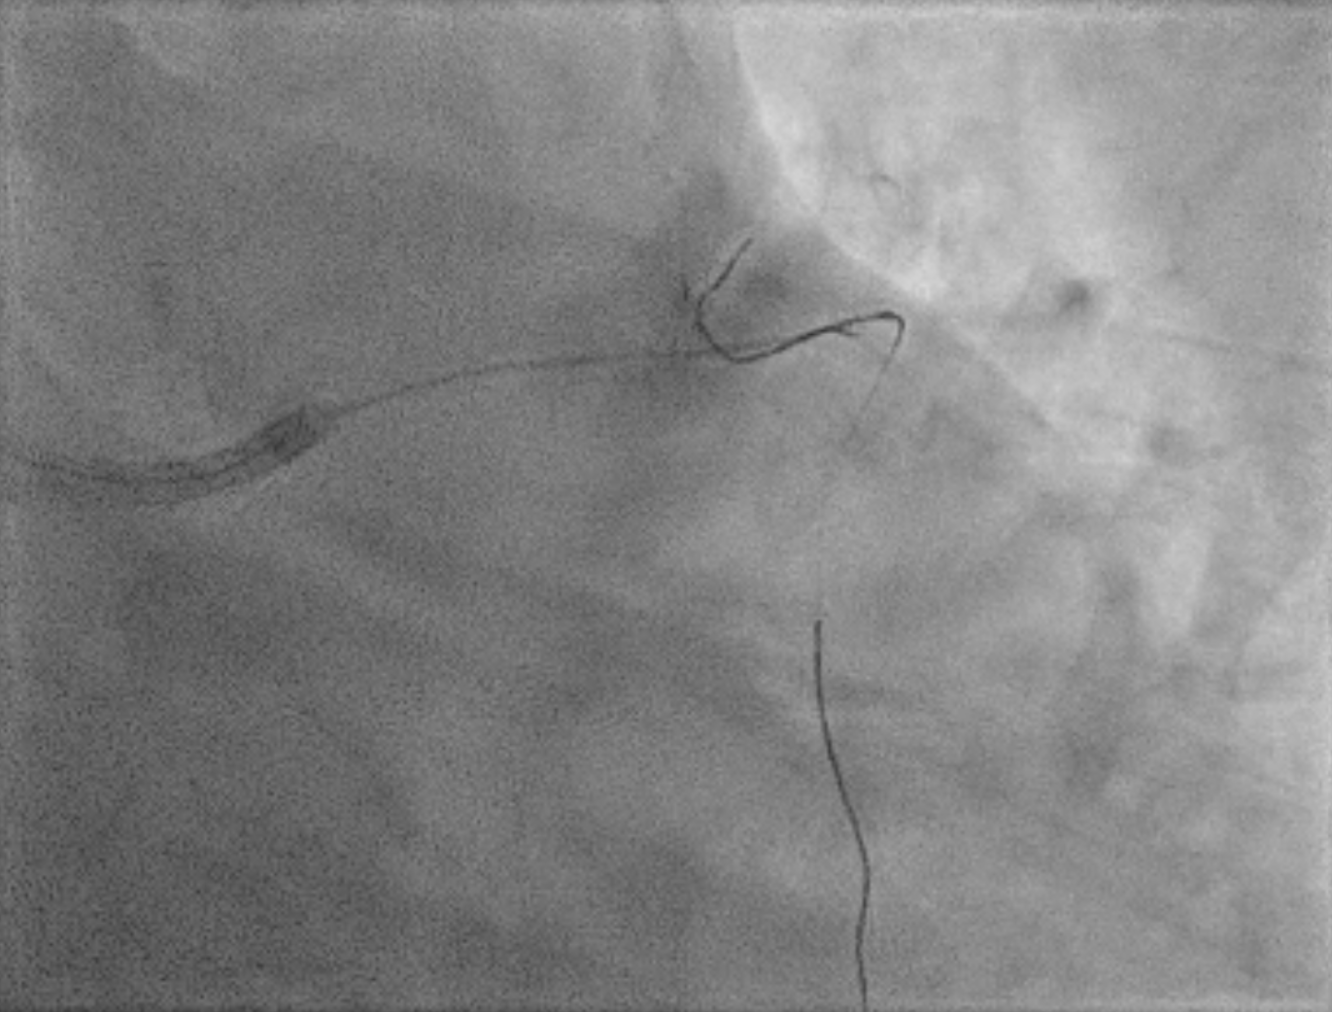

An IVUS-guided PCI of the LAD and RCA was performed via right radial access. An EBU 3.5, 7 Fr guiding catheter engaged the left main, and a Sion Blue wire was advanced to the distal LAD for pre-dilatation with a 2.5 mm NC balloon. Wiring the anomalous RCA from the LAD was challenging due to a retroflexed ostium but was achieved using a reverse wire technique with adual-lumen (Sasuke) catheter and Sion Black wire. Difficulty crossing the mid RCA, likely due to dissection, required multiple wire exchanges before reaching the distal RCA. Lesion preparation used 2.0 mm and 1.5 mm NC balloons in the RCA. IVUS showed LAD diameters of 2.5mm distally with diffuse disease and < 40%plaque burden. A hybrid revascularization strategy was planned. Further preparation involved 3.0 mm and 2.0 mm balloons in the LAD and RCA. DCBs (2.0 ¡¿25 mm in distal LAD; 2.0 ¡¿ 20 mm in RCA) were applied for 60 seconds each. A Xience Sierra 3.0 ¡¿ 38 mm DES was deployed in the proximal–mid LAD,post-dilated with 3.0–3.5 mm NC balloons and optimized with a 4.0 mm POT. IVUS revealed a distal edge dissection, covered with an additional overlapping Xience Sierra 2.75 ¡¿ 23 mm DES. Final IVUS confirmed good stent expansion (MSA6 mm©÷), and angiography showed non–flow-limiting distal LAD dissection with TIMI 3 flow in both LAD and RCA.

3 wiring septal.mp4